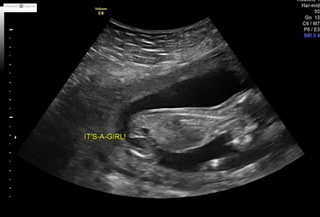

Hi! I had an elective ultrasound at 14 weeks and the tech was confident it is a girl based on both nub and potty shot. I swayed for a girl so praying she is right!! What do you think? P.s. sorry if these pictures are uploaded weird or doubles.. never done pictures before lol Attachment 42861Attachment 42862Attachment 42863Attachment 42862Attachment 42863Attachment 42864